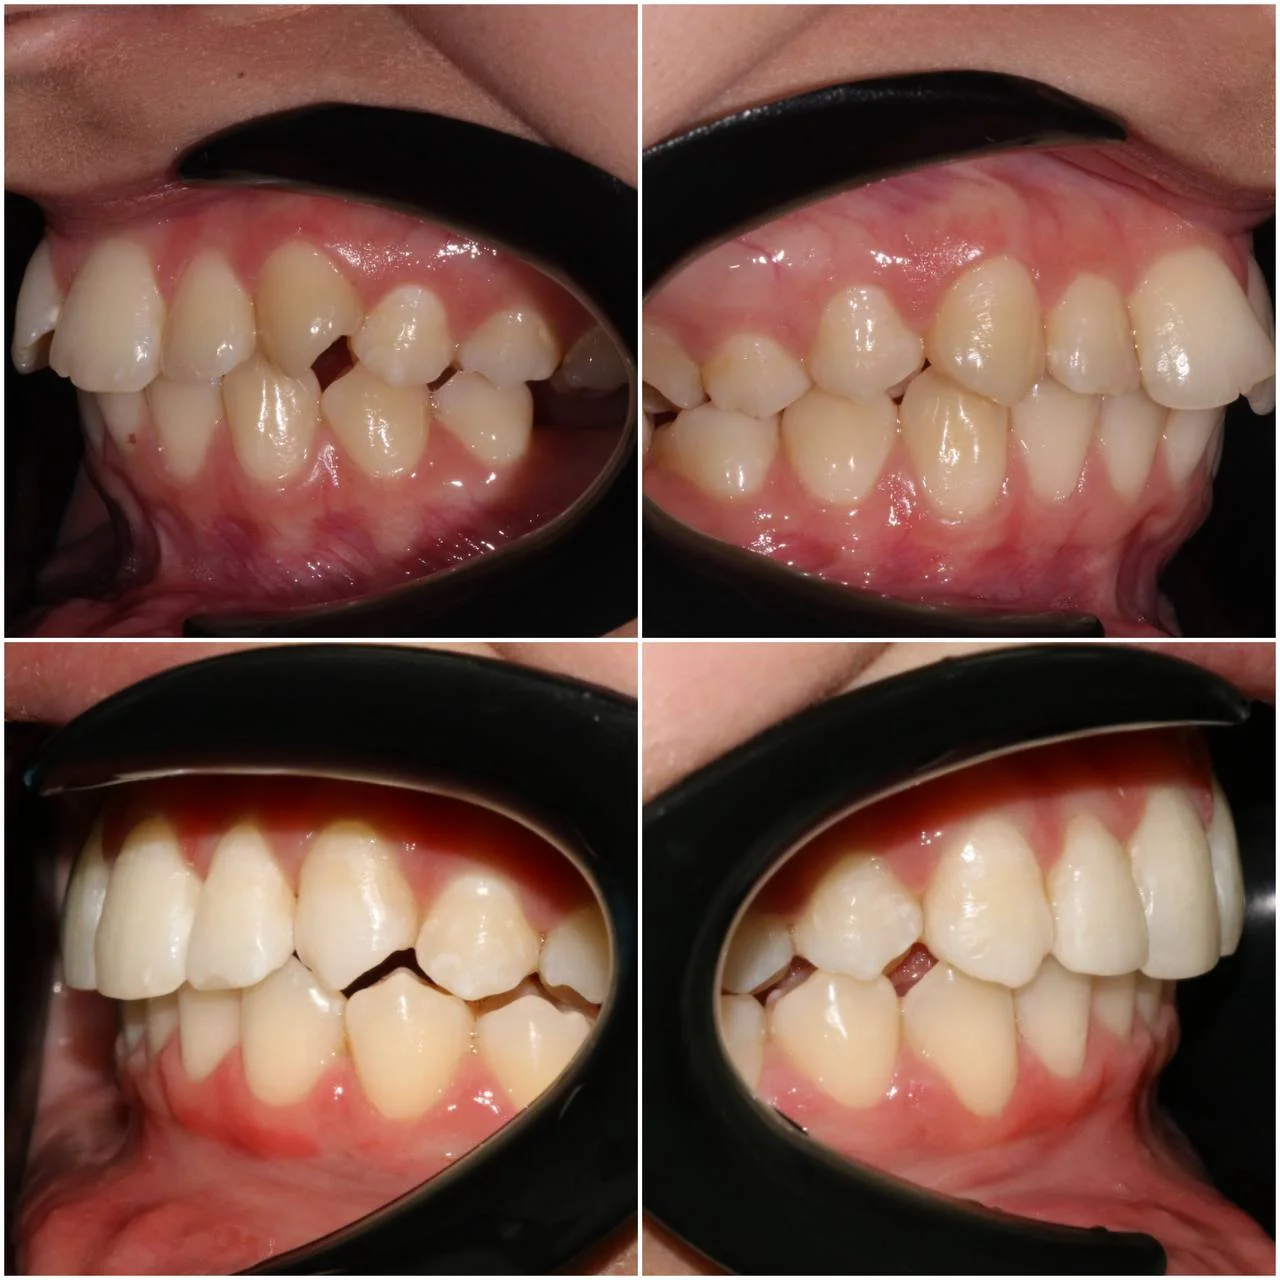

Нарушение соотношения челюстей и неправильное положение зубов — зубные ряды смыкались некорректно, зубы стояли со смещением.

Проблема: В клинику обратилась пациентка — беспокоили неровные зубы и неправильное смыкание. Зубные ряды сходились некорректно, зубы стояли со смещением, что влияло и на внешний вид, и на распределение нагрузки при жевании.

Решение: Поставили элайнеры 3D Smile на обе челюсти. Лечение заняло 4 года и потребовало нескольких последовательных этапов коррекции. Капы менялись каждые 1–2 недели, на контрольных визитах отслеживали прогресс и выдавали новые наборы. Зубы встали в правильное положение, смыкание нормализовалось. Зафиксировали ретейнеры на обе челюсти, изготовили ретенционные капы. Пациентка прошла онлайн-консультацию с ортопедом для оценки дальнейших шагов.